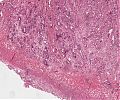

A68a.jpg

Randbereich des Tumors mit angrenzender Mukosa

A68b.jpg

Querschnitt durch den Tumor mit oberflächlicher Ulzeration